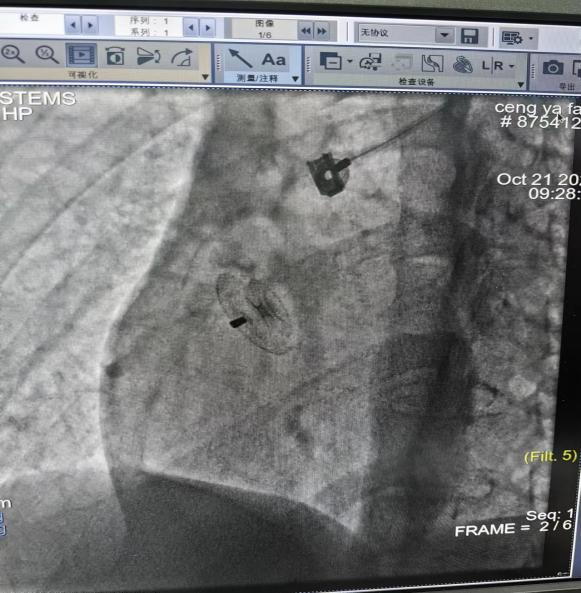

我院心血管内科团队结合患者情况综合分析病情,组织开展多次讨论,并与患者及家属进行充分沟通,最终决定为小曾行卵圆孔未闭封堵术。术前,心血管内科医疗团队为患者完善必要辅助检查、排除手术禁忌。术中,陈小设主任带领团队与介入室的医护人员默契配合,通过微创介入手术,成功将卵圆孔未闭封堵器植入未闭的卵圆孔处,封堵住心脏“小洞”,顺利完成手术!术后复查彩超显示卵圆孔封堵完好,未见残余分流。患者术后恢复良好,顺利出院。出院后,患者头痛症状缓解,摆脱了困扰她多年的头痛烦恼。